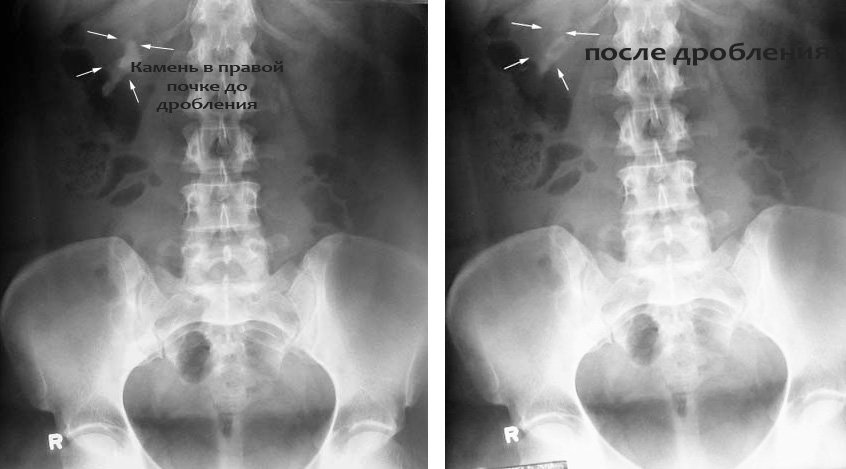

Эффективность лечения дроблением камней ультразвуком в почках и мочеточнике